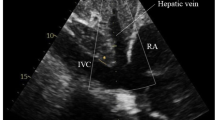

Comprehensive transthoracic echocardiographic examinations were performed using Philips EPIQ 7 G ultrasound system (Philips Healthcare, Koninklijke Philips N.V., Amsterdam, The Netherlands) using variable-frequency 1.0 to 5 MHz sector transducers (Philips X5-1- transducer). All echocardiographic recording included assessment of both the left and right heart. Including established standard measures, we assessed left ventricular end-diastolic volume, left ventricular end-systolic volume and left ventricular ejection fraction, using standardized Simpson’s method in both four and two chamber view. Additional collected parameters contained left atrial volume, pulsed Doppler transmitral flow profiles, pulsed wave Doppler placed in the left ventricular outflow tract, and tissue Doppler Imaging on the mitral annulus. Right heart function was assessed using right ventricular end-diastolic volume, tricuspid annular plane systolic excursion, and fractional area change of the right ventricle. The velocity flow profile in hepatic veins was measured by pulsed wave Doppler from the subcostal view and the pulsed wave Doppler flow profile of the upper right pulmonary vein was recorded. Strain analysis was performed and the Myocardial Performance Index (Tei-Index) was calculated. The size of the IVC was determined with the patient in the supine position using 2DE images from the subxyphoidal view. The breathing-corrected diameter was measured perpendicular to the long-axis of the IVC, proximal to the junction of the hepatic veins, 2.0 cm proximal to the ostium of the right atrium, assessing IVC volume as largest deflection and shortest distention.

Three-dimensional echocardiography

Single full-volume 3DE loop data were acquired using a subxyphoidal view with the patient in a supine position. 3DE full-volume images of standardized breathing-corrected sounding IVC were recorded, placed approximately 2.0 cm (0.79 inches) proximal to the ostium of the right atrium and perpendicular to the long-axis reference of the IVC. Digital cross-sectional image reconstruction was done using available software (Philips QLAB 10, QLAB Ultrasound Cardiac Analysis, Koninklijke Philips N.V., Amsterdam, The Netherlands) for cardiac 3D quantification. IVC cross-sectional images were scaled into a vertical diameter and in a second diameter perpendicular to the vertical diameter. All measurements were compiled for their largest and smallest deflection. In addition, IVC area was quantified in the cross-sectional images to picture frequent irregular IVC morphology. Schematic presentation of exemplary echocardiographic examination with ultrasound images in cross-sectional and longitudinal-sectional view of IVC is shown in Fig. 1.

Schematic visualization of echocardiography technique used in this study. This figure illustrates the standardized consistent measurement of inferior vena cava (IVC) and vena cava inferior volume, defined as the product of largest deflection and shortest distention, used in this study. Transducer placed in predefined standardized subxyphoidal position. Patient in supine position and IVC diameters are measured, breathing corrected, perpendicular to IVC long-axis, proximal to the junction of the hepatic veins, 2.0 cm proximal to the ostium of the right atrium, assessing IVC volume as largest deflection and shortest distention

A total of 60 patients were screened and fulfilled inclusion criteria for study participation (Table 1). All patients underwent complete clinical assessment including Swan-Ganz RHC followed by immediate 2DE and 3DE (Philips EPIQ 7G) examination including inferior vena cava (Fig. 1). Echocardiographic characteristics and catheterization data are presented in Table 2. All patients were assessed using 2DE, but 3DE data from three patients had to be excluded for poor image quality. Our inter- and intra-observer variability with 8% and below 5%, was comparable to similar studies in the literature. The results of the correlation analysis are presented in Table 3, including sample size for each variable.